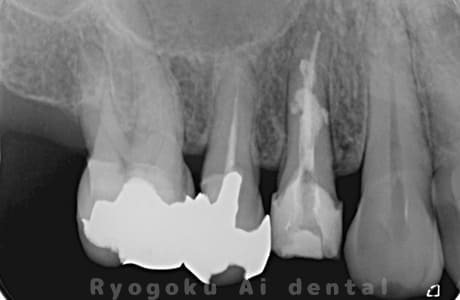

根管内の異物

- 原因

- 根管内異物(ファイル破折)による慢性根尖性歯周炎

- 治療期間

- 3ヶ月

- 治療内容

- マイクロスコープを使用した根管内異物除去並びにマイクロエンド

- 治療費用

- 121,000円(ファイル除去費用も込み)

他院で細い器具(ファイル)が根管内に破折した状態で、咬合痛を主訴に来院された患者様です。ファイルをマイクロスコープ下で除去し、根管治療を行ないました。

<リスク・副作用>

術後は痛み、腫れ、痺れなどの副作用が生じる場合があります。症状が再発する可能性があります。